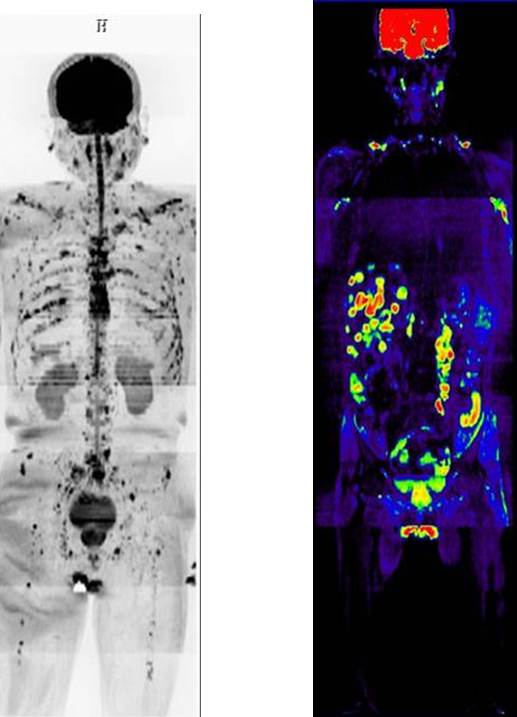

三、全身DWI技术(类“PET”)

1、全身DWI主要用于血液系统肿瘤的全身评价,血液系统恶性肿瘤在全身DWI上可表现为骨髓弥漫性水分子活动受限;全身DWI有助于晚期转移灶的发现。

2、全身其他部位原发肿瘤筛查,转移瘤筛查,淋巴结转移筛查,恶性肿瘤分期。

骨髓瘤患者全身骨质多发破坏 |

肝脏多发转移并双侧颈部、腋窝淋巴结多发转移 |